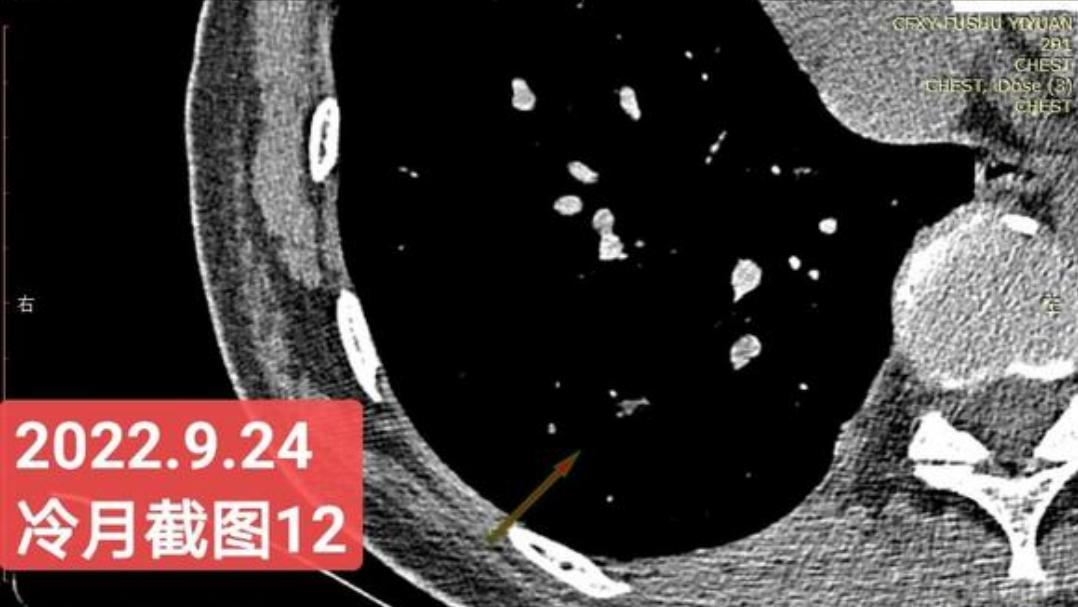

非常感谢戴主任和冷月等几位吧主的无私奉献,你们牺牲自己的休息时间,为广大患者排忧解难,你们对待病人,如同亲人一样,真的好感动!上次,在贴吧里咨询过戴主任关于我的肺结节情况,戴主任说,我右肺下叶那个结节高危。心里好害怕,距离上次CT间隔三个月,我又做了肺部CT,这次还要劳烦戴主任以及吧主们,帮我看看我的肺结节,严重吗?需要马上手术吗?

我昨天把我五次肺部CT电子版以及报告,发给了冷月吧主,昨天晚上,冷月吧主就为我截好图,发给我,非常令我感动,谢谢您冷月吧主,您辛苦了,您要多休息,不要太辛苦了。

我是21年7月做肺部CT,报告给报出0.5厘米肺结节。(但大夫说,20年就已经有那个肺结节了,因为小,报告没给报)。自发现肺结节后,吃了四个月中药,结节没有缩小,反而增大了。今年8月1日开始到现在,又吃了近两个月的蒙药了。 结节还是没有缩小,反而在增大。21年7月到现在,复查过3次肺部CT了。结节一直在增大。最近一次复查时间是2022年9月24日。

上次找戴主任贴吧咨询过,主任说我右肺下叶那个结节高危,距离上次CT,到现在三个月复查肺部CT。所以9月24日又复查做了肺部CT。

右下肺结节高危,肺窗已经到亚实性阶段CTR>0.5,纵膈窗可见实性,目前已经不属于异质混磨,而且PSN亚实性结节。